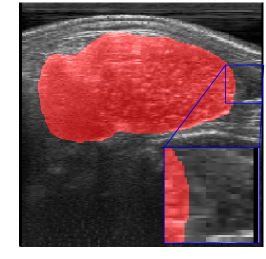

Figs. 2 and 3 present examples that illustrate the challenges of semantic segmentation methods. The trees in Fig. 2 show that in most images the foreground covers fewer pixels than the background (class imbalance). Besides, trees have edges that are difficult to label, and some pixels may be incorrectly labeled. Fig. 3 also illustrates the labeling challenge, in which some parts of the object are not visible in the image due to noise when capturing images.

Rib Eye Area (REA). This image dataset consists of ultrasound images of the Longissimus dorsi muscle between the 11th and 13th ribs of cattle. The goal is to automatically calculate the rib eye area (REA), an important region for decision making during cattle breeding. The main challenge is the uncertainty in the REA annotation, since the image is noisy and even experts have difficulty in delimiting the borders of this region. Fig. 3 presents examples of images and the annotation made by a specialist. We can observe that some borders are absent and depend on the subjectivity and knowledge of the annotator. To evaluate the segmentation methods, 76 images with resolution were obtained and labeled by an expert. Due to the number of images, the division of the images in training and testing followed 5-fold cross-validation.

REA dataset. This image dataset has high uncertainty during labeling due to noise from the ultrasound image. In some cases, the border of REA is not completely visible and must be estimated by the specialist. Therefore, the proposed approach becomes essential to obtain accurate segmentation at the edges. The segmentation examples in Fig. 6 show that the baseline was not able to define the REA correctly due to the uncertainty of the labeling. On the other hand, the proposed approach presents results close to the specialist in regions that the border needs to be estimated.